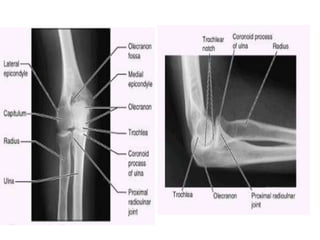

1.- Es sinovial de tipo bisagra

2.- Se sitúa 2 a 3 cm debajo de los

epicóndilos del húmero.

COMPONENTES

• Tróclea

• Cóndilo esférico del húmero

• Escotadura troclear del cúbito

• Cara superior de la cabeza del

radio.